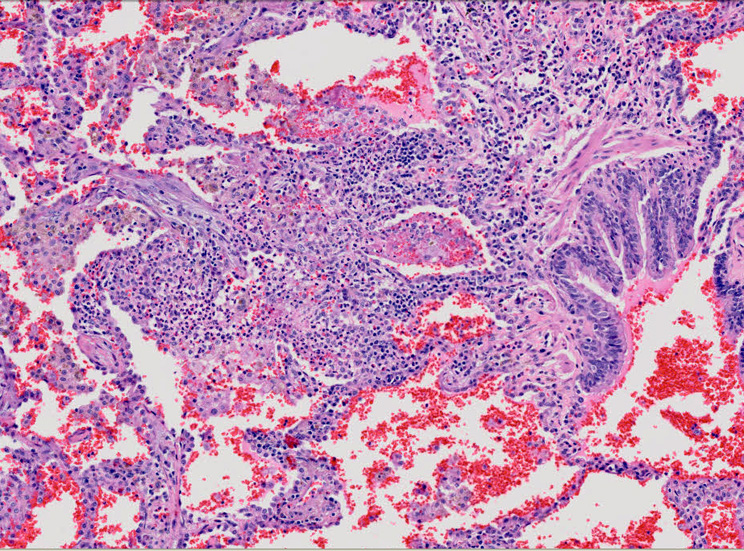

肺毛細血管炎 capillaritis

肺胞壁に多数の好中球浸潤。肺胞腔内に出血。 capillaritisが起こるWegener' granulomatosis劇症型には, なかなか肉芽腫性病変を見つけることは難しい

capillaritisの組織所見*17

Fig.01 capillaritisと肺胞出血Fig.02 Fig.01拡大像